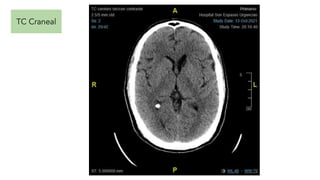

TC Craneal. No signos de sangrado agudo intracraneal. Lesión hipodensa en cabeza del

caudado-adyacente al asta anterior del VLI, que por las características es probablemente en relación con

una lesión crónica secundaria a antigua ¿isquemia,sangrado? Sistema ventricular de tamaño y

morfología normal. Línea media centrada. Cisternas basales permeables. Conclusión: Sin evidencia de

signos de hipertensión intracraneal.

TC Craneal. Nosignos de sangrado agudo intracraneal. Lesión hipodensa en cabeza del caudado-adyacente al asta anterior del VLI, que por las características es probablemente en relación con una lesión crónica secundaria a antigua ¿isquemia,sangrado? Sistema ventricular de tamaño y morfología normal. Línea media centrada. Cisternas basales permeables. Conclusión: Sin evidencia de signos de hipertensión intracraneal. Punción lumbar PIC NRL. No relación con clínica actual. Valorar PL.